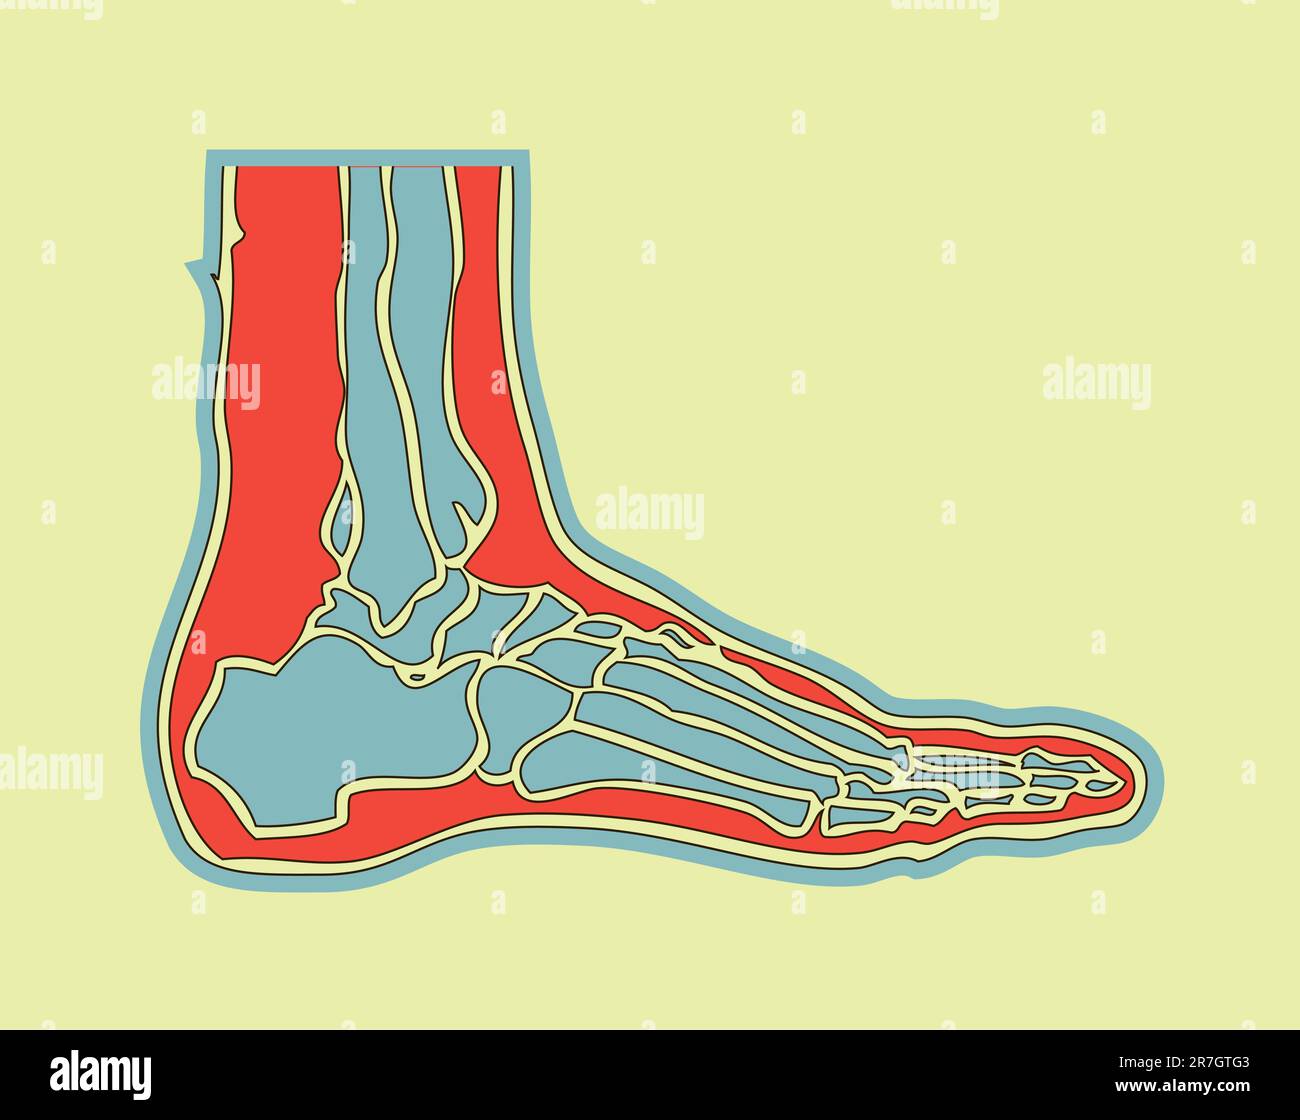

RF2J65WT4–Anatomie du pied. Pied humain avec le nom et la description de tous les os et sites. Vue de dessus et vue latérale. Arcs des pieds. Anatomie du squelette. Vecteur

RFHNA1H2–L'os du pied humain ont un signal rouge. Cette illustration à propos de la douleur de pied.

RF2R3WKY1–Illustration médicale des principales parties des os du pied en vue latérale, avec annotations.

RF2X200ED–L'anatomie de l'articulation de la cheville. Région talocrurale ou os sauteur. Partie du corps humain où le pied et la jambe se rencontrent. Fascia plantaire et tendon d'Achille

RF2B74PR1–Le pied est construit sous la forme d'une demi-dôme ou d'une demi-voûte, d'un dessin vintage ou d'une gravure.